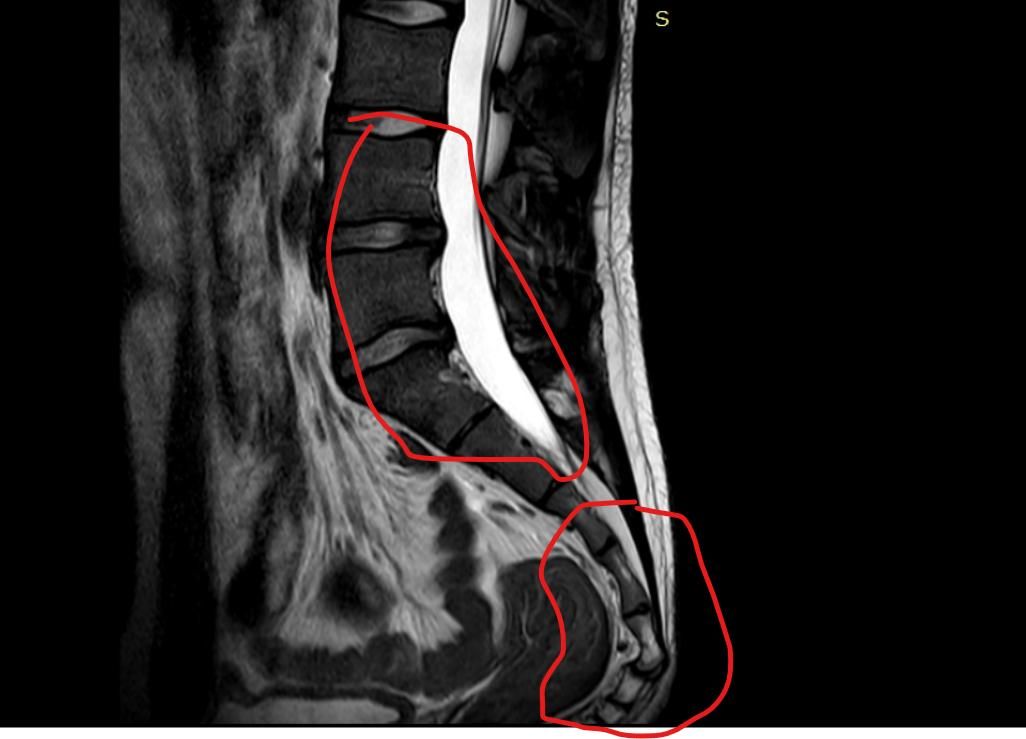

제가 7월28일에 어깨 수술이후 골반쪽이 계속 아프더라구요 그래서 엠알아이 찍어봤는데 꼬리뼈 돌출이됬습니다 그 어깨 수술이후 자세 불균형 때문에 그럴수가 있나요 ? 그리고 동그라미 한 저 허리쪽은 왜 하얀건가여ㅛ

동그라미 친 허리 쪽의 "하얀 부분은 MRI에서 뇌척수액(CSF)" 으로, 신경을 싸는 정상 구조입니다.

다만  직접적인 원인이라기보다는 유발·악화 요인 으로 보는 게 정확해요. 어깨 수술 후에는 통증 때문에 한쪽으로 몸을 기울이거나, 보호 자세로 오래 지내게 되는데요. 그러면 척추–골반 정렬이 틀어지고, 특히 오래 앉아 있거나 비스듬히 기대는 습관이 생기면 꼬리뼈에 지속적인 압력이 가해질 수 있습니다. 원래 약간의 구조적 문제나 유연성 문제가 있던 상태라면, 이런 자세 변화로 꼬리뼈 돌출이나 통증이 드러나거나 심해질 수 있어요. 동그라미 친 허리 쪽이 하얗게 보이는 건 정상적인 MRI 소견입니다. 이건 병변이 아니라 척수액(뇌척수액)이에요. MRI 종류 중 T2 영상에서는 물 성분이 하얗게 보이는데, 척수 신경을 둘러싼 액체가 그렇게 보이는 겁니다. 즉, 하얀 것 자체는 문제 아닙니다. 지금 단계에서는 자세 교정, 골반·코어 재활, 앉는 습관 조절이 중요하고, 꼬리뼈 통증이 계속되면 도수치료나 재활의학과 쪽 접근이 도움이 됩니다.

또한 올려주신 사진의 MRI에서 하얀 음영이 보이는 것은 척추 사이를 통과하는 척수입니다.

도넛 방석과 같은 압력을 줄여주는 도구를 사용하시길 바라며 사진상 표시된 부위는 척추관이며 뇌척수액과 신경이 지나가는 통로로 액체와 같은 성질이 흐르기에 하얗게 표시됩니다^^